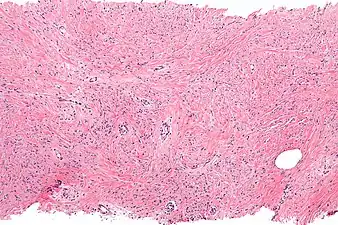

| Micrograph of mammary myofibroblastoma. H&E stain. | |

Intermed. mag. Mammary myofibroblastoma

Medical imaging may suggest but cannot prove that a tumor is MFB. Mammography, computed tomography scans, and magnetic resonance imaging of mammary[1][12] and extramammary[1][13] MFB typically show well-defined and well-circumscribed tumors which in almost all cases have no calcifications; these results suggest that the tumor is not malignant but do not indicate which type it might be. The diagnosis of MFB depends on the microscopic histopathology (i.e. appearances after proper tissue preparation and staining) of its pre-surgery biopsied issues. As shown in the upper image and the two images in the Additional images section seen below, both mammary and extramammary MFB tissues contain spindle cells, variable numbers of adipocytes (i.e. fat cells) and broad sheets or, less often, thick bundles of collagen fibers.[5] About 4% of cases have an epithelial tumor cell-like morphology,[5] i.e. the tissues are composed predominantly of epithelioid cells variably mixed with a minority (10% to 40%) of round, polygonal, and spindle-shaped cells.[19] Unlike malignant tumors, MFB tumors do not have: a) atypical cells except in the rare cases which contain small clumps of multinucleated cells; b) rapidly proliferating cells as defined by measuring the proliferative index (i.e. fraction of cells undergoing mitosis); or c) areas of necrosis (i.e. areas of dead or dying cells).[16] Microscopy of tumors in the spindle cell lipoma tentative variant of MFB show a mixture of mature fat cells, ropey collagen, and spindle cells in a myxoid (i.e. background connective tissue that stains blue or purple rather than the red of normal connective tissue) matrix.[18] The blood vessels in these tumors often appear hyalinized.[16] Tumor tissues in the tentative cellular angiofibroma variant of MFB contain spindle cells in all cases, fat cells in ~50& of cases, mast cells, peri-vascular infiltrates of lymphocytes, pleomorphic cells in some cases, and cells with some features of the malignant sarcoma cells in sarcoma tumors in rare cases. (The presence of these sarcoma-like cells does not seem to impact the prognosis of this variant.) All of these cells are in edematous-to-fibrous stromatous tissue.[16]